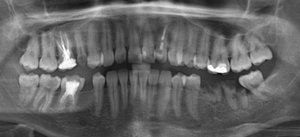

После 20 лет службы стала шататься коронка верхних передних зубов. Ее сняли и мой врач, так как он имлантолог, стать толкать меня на имплантацию (в Индии). Но остатки зубов еще есть, хотя есть инфекция и, как он утверждает, киста на одном корне.

Проясните ситуацию, а именно — можно ли опять поставить штифты и новые коронки или только импланты?

Оба зуба однозначно удаляются.

Показания к имплантации абсолютные, рекомендую выбрать качественную систему и проконсультироваться с несколькими имплантологами.